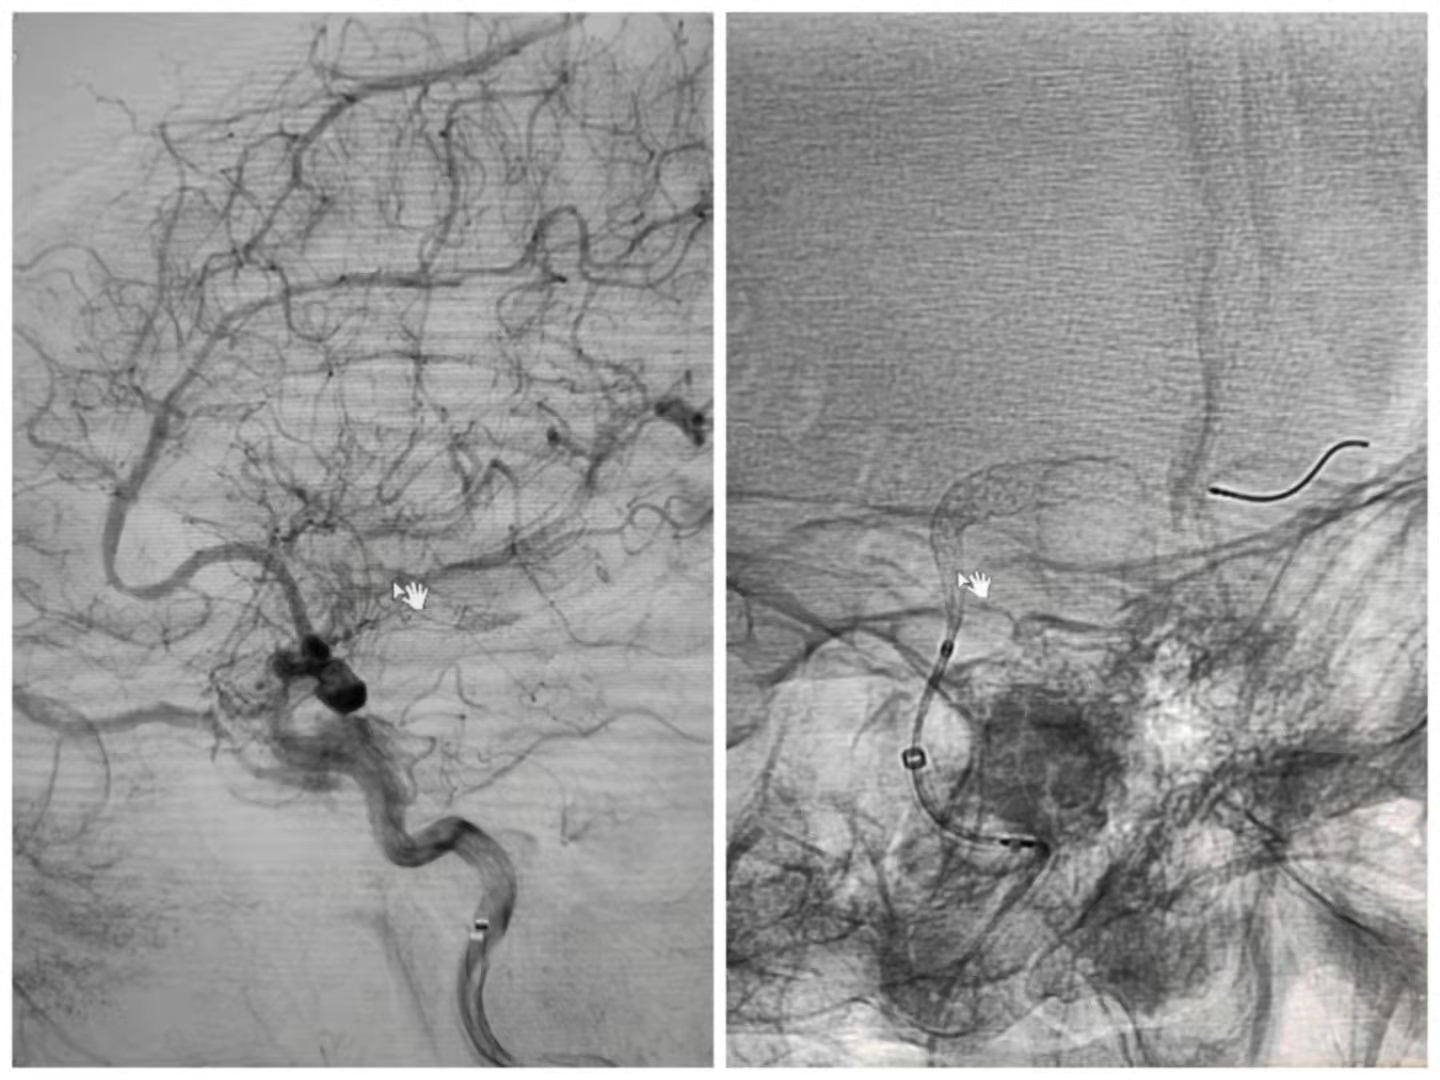

患者是一名64岁女性,因头痛在当地旗医院查CTA诊断为左侧后交通段宽颈动脉瘤,随后到我院神经外科进行治疗。颅内动脉瘤被称为颅内不定时炸弹,是常见的颅内血管疾病,严重威胁人类的生命健康。传统的治疗方法对于复杂的颅内动脉瘤(如巨大动脉瘤、宽颈动脉瘤及血泡样动脉瘤)治疗难度大、风险高且易复发。针对病人的情况,神经外科组织术前讨论,最终决定为病人实施血管导向装置(密网支架)植入术,邀请宣武医院叶明主任医师指导手术,我院神经外科副主任医师呼和巴特尔实施手术,手术过程顺利,术后患者意识清醒,无神经功能障碍,造影显示动脉瘤内造影剂明显滞留,身体恢复较好,活动自如。